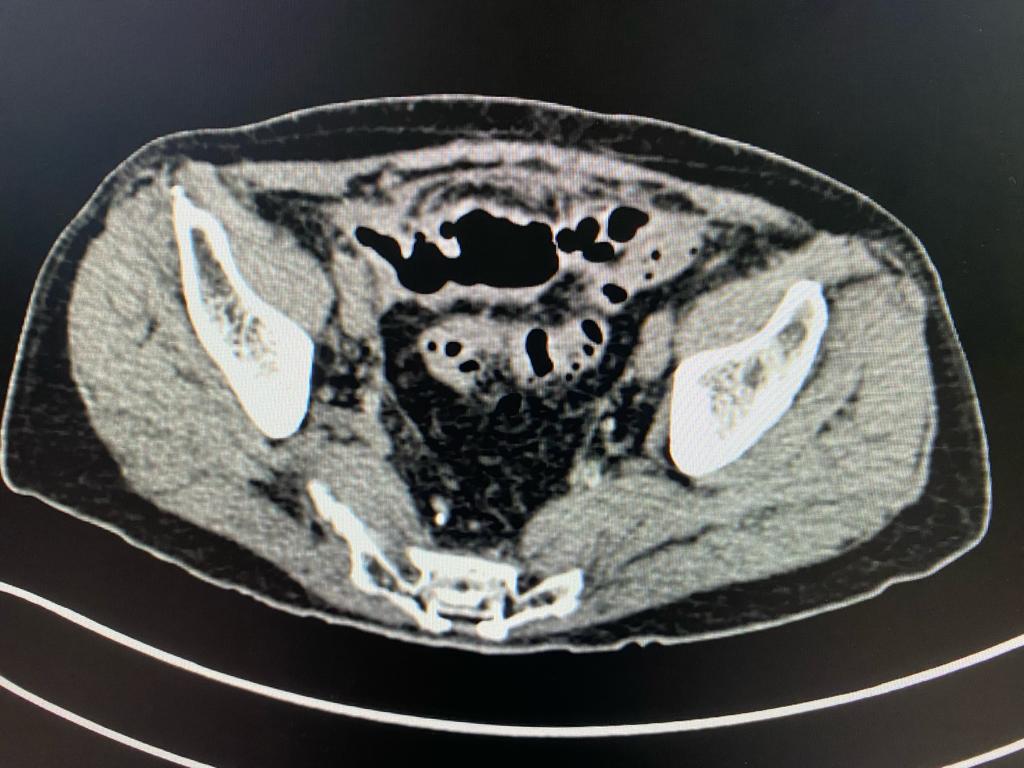

After admission, we reviewed the history, investigations, sequence of events and old CT scan. We suspected colonic diverticulosis with perforation as the original reason for sepsis. We repeated the CT scan of abdomen and pelvis which showed a pelvic abscess along with a sigmoid colonic diverticular phlegmon confirming diverticular perforation. The drain placed during previous laparoscopy was out of position. After a multidisciplinary meeting, treatment plan was charted out. The original drain was used to guide another drain deep in the pelvic abscess cavity under radiological guidance thus ensuring free drainage. The antibiotics were adjusted based on culture sensitivity of the intraabdominal pus. There were multiple highly resistant organisms and very few antibiotics were available for treatment. Hence the definitive surgery was deferred. Patient recovered and was sent home on intravenous antibiotics and drainage catheter.